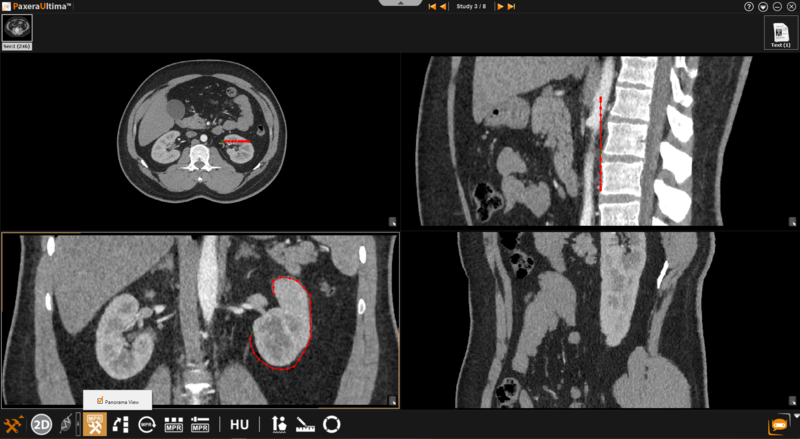

Panorama View

The panorama view is only available when the curved mode is in use. This setting ensures that the panoramic view of the original curve will remain constant on the resultant image regardless of manipulatons made in the other image windows. If this option is not selected, manipulations made in the other windows after the curve is drawn will affect the resultant image. The panorama view is enabled by default.

Follow the instructions below to change the image view to 'Panorama View':

Click on the 'MPR Settings' button from the toolbox panel at the bottom of the screen

Select the 'Panorama View' button from the menu.

Draw the curve and observe the panoramic view on the resultant window.